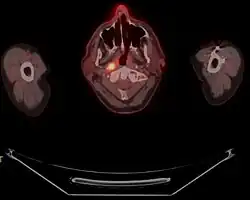

También se utilizan para su estudio la TAC y en ocasiones, previa a la cirugía, la RMN.